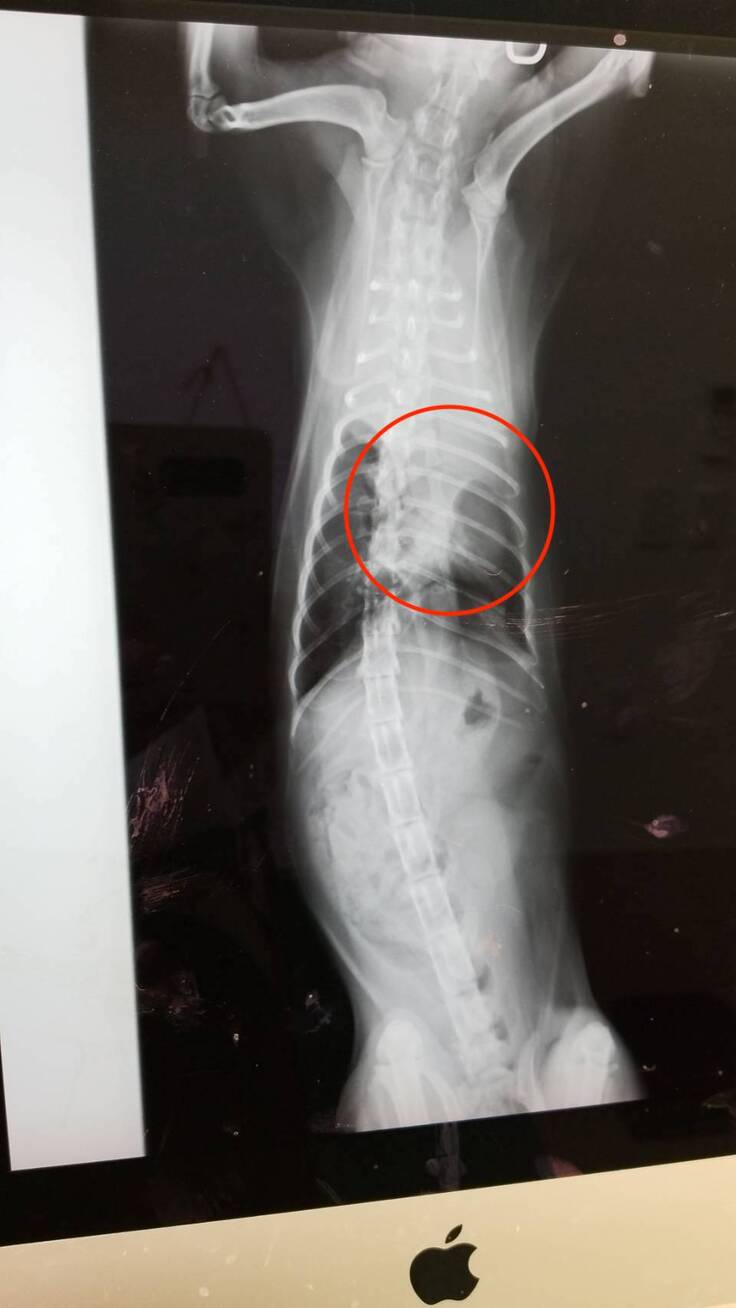

▼レントゲン写真

レントゲン写真からは、胸水が肺を圧迫している様子がわかるかと思います。